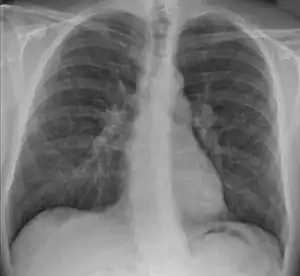

![]() | |

| Chest X-ray showing the typical nodularity of sarcoidosis, predominantly in the hila of the lungs. | |

Chest radiograph changes are divided into four stages:[105]

- bihilar lymphadenopathy

- bihilar lymphadenopathy and reticulonodular infiltrates

- bilateral pulmonary infiltrates

- fibrocystic sarcoidosis typically with upward hilar retraction, cystic and bullous changes

Although people with stage 1 radiographs tend to have the acute or subacute, reversible form of the disease, those with stages 2 and 3 often have the chronic, progressive disease; these patterns do not represent consecutive "stages" of sarcoidosis. Thus, except for epidemiologic purposes, this categorization is mostly of historic interest.[28]